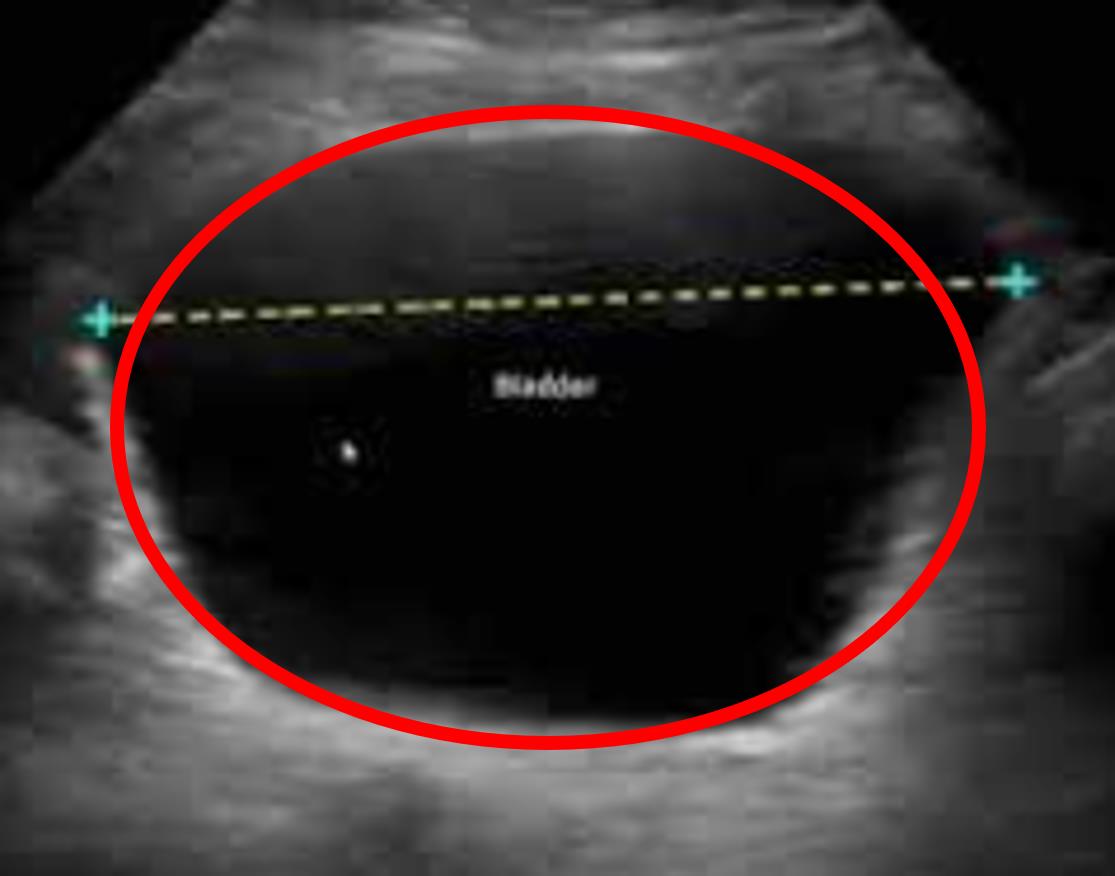

A 61-year-old G2P2 woman presents with a 1 month history of incontinence. She has been leaking urine at night, especially in the later hours of the night before she wakes up. She has not noticed any leakage with coughing, laughing, or urge to urinate. She has tried drinking less water and doing pelvic floor exercises without benefit. Her medical is significant for diabetes as well as 2 spontaneous vaginal deliveries with an epidural for pain control. Her temperature is 98.6°F (37.0°C), blood pressure is 115/70 mmHg, pulse is 70/min, and respirations are 12/min. A bladder scan is obtained with the results shown in Figure A and a post-void residual volume of 525 cc. Which of the following is the most appropriate next step in management?

Figure/Illustration A is a bladder ultrasound demonstrating increased urine in the bladder (red circle). This finding is consistent with overflow incontinence.